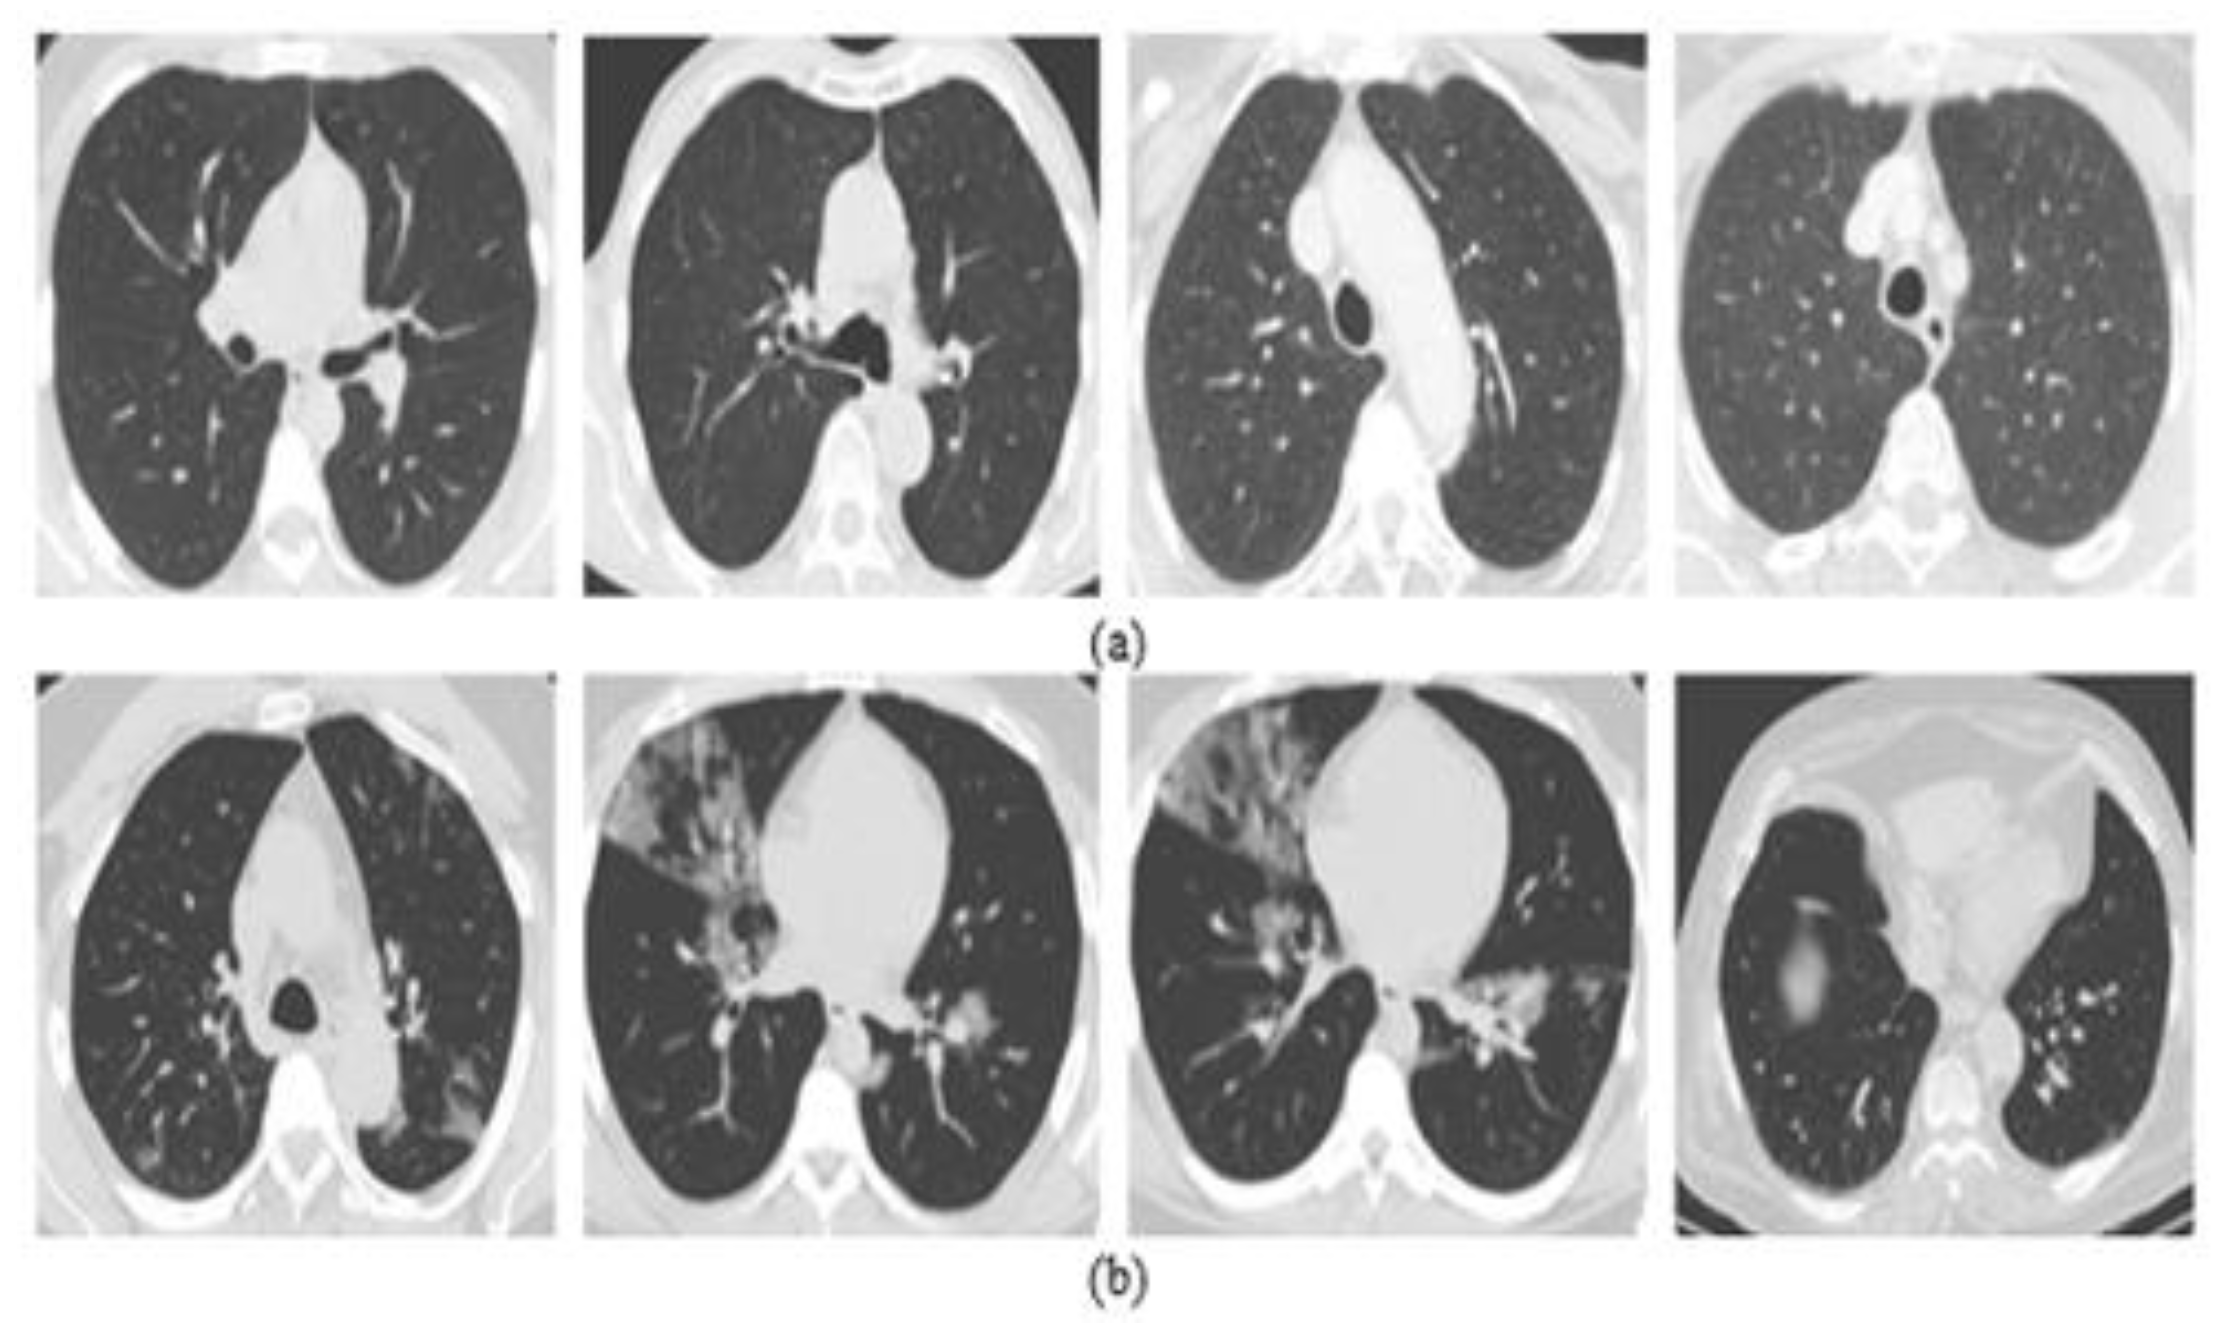

5.2. Results on CT